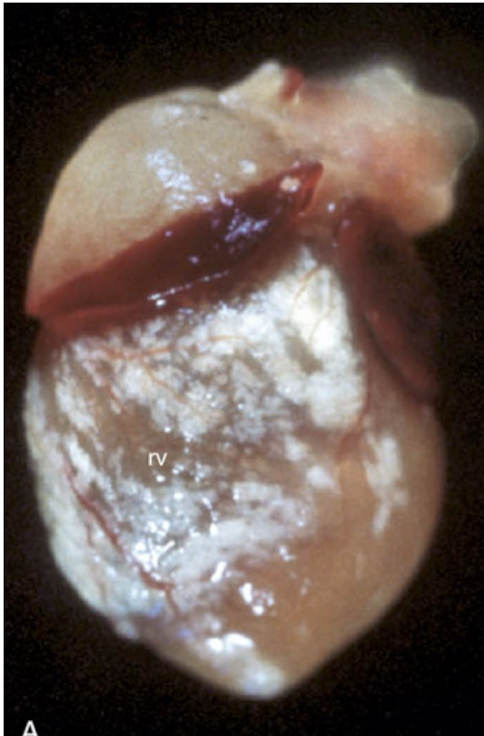

What is this showing?

fibrinous to fibrinosuppurative pericarditis

clostridium chauveoi (black leg)

fibrinous pericarditis due to Glasser’s disease

traumatic reticulopericarditis aka hardware disease